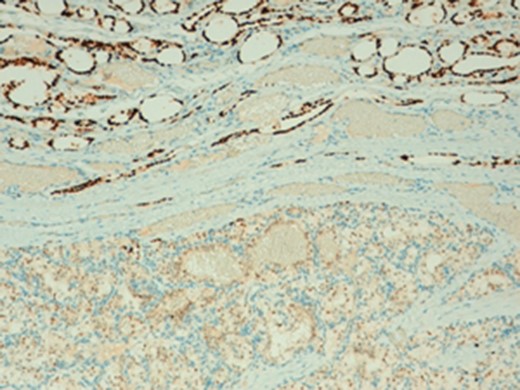

The histologic diagnosis was aided by the use of immunohistochemistry which was positive for PAX8 (Fig. 4) and CD10, and negative for thyroid transcription factor 1 (TTF-1) (Fig. 5), vimentin and chromogranin.